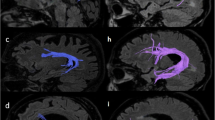

Figure 1 shows the results of the voxel-wise comparisons of the pMD, nMD, and gmMD maps between the AD and MCI groups (Fig. 1a) and between the AD and CN groups (Fig. 1b) based on one-way ANOVA tests. Compared to the MCI patients, the AD patients had increased pMD values mainly in the temporal and frontal lobes. The AD patients also had increased nMD values (AD > MCI) mainly in the temporal lobe. Moreover, we found that the AD patients had increased gmMD values (AD > MCI) predominantly in the right superior temporal gyrus, the left limbic parahippocampal gyrus white matter, and the left superior and medial frontal gyrus. There were no significantly decreased MD values in the gmMD, pMD, and nMD maps from the patients with AD as compared with that of the MCI subjects. The detailed results are summarized in Table 2.

Results of the voxel-wise comparisons of mean diffusivity (MD; gmMD, nMD, pMD) between the Alzheimer's disease (AD) and mild cognitive impairment (MCI) groups (a) and between the AD and cognitive normal (CN) groups (b) using one-way ANOVA tests. There were no decreased MD values for all three maps of gmMD, pMD, and nMD in the patients with AD as compared with that of the MCI or CN patients. There were no significant differences between the MCI and CN patients

Compared to the CN subjects, the AD patients had increased pMD values mainly in the temporal gyrus. The AD patients also had increased nMD values (AD > CN) mainly in the temporal gyrus. Moreover, we found that the AD patients had increased gmMD values (AD > CN, Fig. 1b) predominantly in the left limbic parahippocampal gyrus, the left limbic uncus, the left and right temporal subgyrus, and the right middle temporal gyrus. These detailed results are summarized in Table 3.

The significant regions that overlap in all three DT-MRI sets (positive gradients, negative gradients, and geometric mean) as well as those regions that differ are listed in Table 6 for the MD (pMD, nMD, and gmMD) and in Table 7 for the FA measures. The overlapping regions of increased MD in the AD patients relative to the MCI subjects (AD > MCI) included the right superior temporal gyrus and left limbic parahippocampal gyrus. In contrast, the nonoverlapping regions of increased MD in the AD patients relative to the MCI patients (AD > MCI) included: the right occipital subgyrus and the left medial and superior frontal gyrus for the gmMD; the right middle occipital gyrus for the nMD; the right middle temporal gyrus, the left medial frontal gyrus, the right occipital cuneus, the left parietal supramarginal gyrus, the left limbic parahippocampal gyrus, the left limbic uncus, the right insula, and the right middle frontal gyrus for the pMD.

Similarly, the overlapping regions of increased MD in the AD patients relative to that of the control subjects (AD > CN) included the left limbic parahippocampal gyrus and right middle temporal gyrus. In contrast, the nonoverlapping regions of increased MD in the AD patients relative to that of the control subjects included: the left limbic uncus and the left and right temporal subgyrus for the gmMD; the left and right temporal subgyrus and the right sublobar insula for the nMD; the right temporal subgyrus, the right occipital subgyrus, the right occipital cuneus and the right inferior occipital gyrus for the pMD. Because the gmFA and nFA differences between the AD patients and the other two groups of subjects were not significant, there were no overlapping regions for the FA measures.